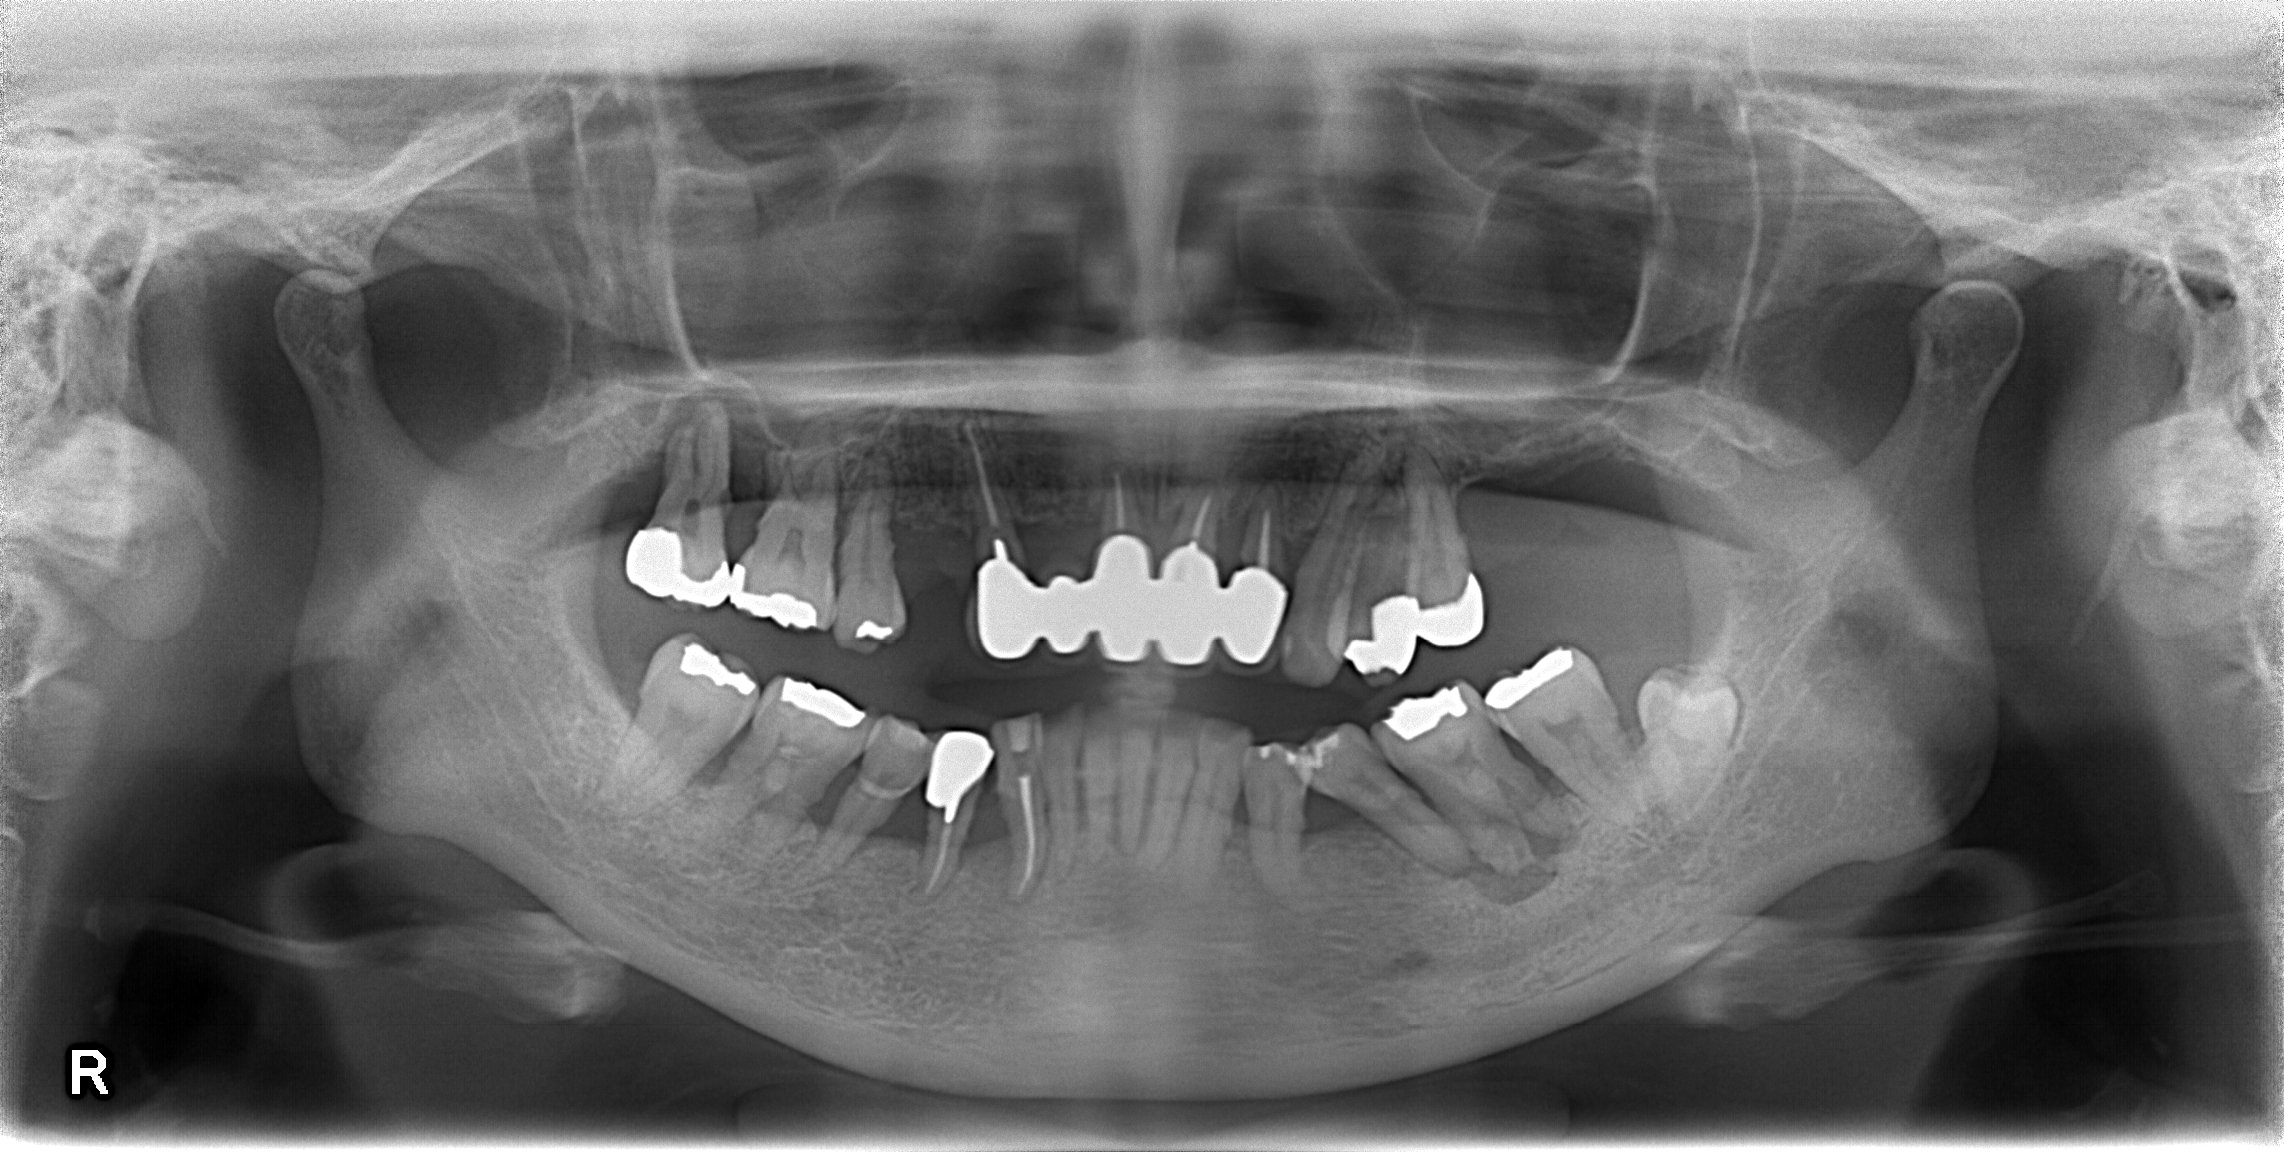

4年前から診させていただいている患者さんです。

全体的に歯周病でした、根本的に解決を図ろうと思うと、抜歯になってしまう歯が多数存在しました。

しかし、患者さんと話し合いの末、なんとかいける歯は残して歯周病をコントロールし、いけるところまでいこう、という治療計画に決定しました。

残すのが難しい状態だった2本の上の奥歯、下の奥歯を1本抜歯、あとは保険適応のブリッジと部分床義歯を製作しました。

この状態で早4年、治療終了時点から1本しか歯は抜けておりません、しかもその抜けた歯も、抜けた当日に隣の歯と接着させることで治療終了とし、日常生活になんら影響を及ぼすことなく終えることができました。